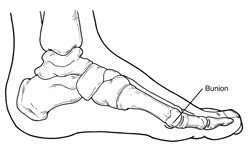

A bunion (also referred to as hallux valgus or hallux abducto valgus) is often described as a bump on the side of the big toe. But a bunion is more than that. The visible bump actually reflects changes in the bony framework of the front part of the foot. The big toe leans toward the second toe, rather than pointing straight ahead. This throws the bones out of alignment – producing the bunion’s “bump.”

Bunions are a progressive disorder. They begin with a leaning of the big toe, gradually changing the angle of the bones over the years and slowly producing the characteristic bump, which becomes increasingly prominent. Symptoms usually appear at later stages, although some people never have symptoms.

Bunions are readily apparent – the prominence is visible at the base of the big toe or side of the foot. However, to fully evaluate the condition, the foot and ankle surgeon may take x-rays to determine the degree of the deformity and assess the changes that have occurred.

A variety of surgical procedures is available to treat bunions. The procedures are designed to remove the “bump” of bone, correct the changes in the bony structure of the foot, and correct soft tissue changes that may also have occurred. The goal of surgery is the reduction of pain.